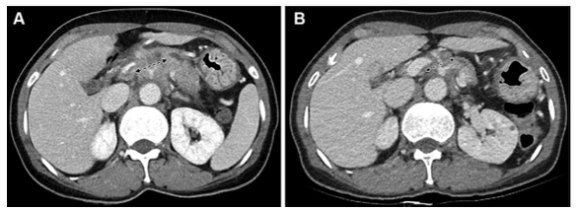

圖 一名54歲胰腺導管腺癌患者的圖像,為第一組的代表性病例(CT和CA 19-9反應者)。(A) 基線對比增強CT圖像顯示胰腺體部有一個30毫米的腫塊,腹腔動脈和肝總動脈被包圍(箭頭)。該腫塊為局部晚期可切除狀態。基線CA 19-9水平為391.9 U/ml。(B)使用5-氟尿嘧啶、亮丙瑞林、伊立替康和奧沙利鉑或FOLFIRINOX一線治療8周后獲得的后續對比增強CT圖像。由于腫塊的大小略微下降到27毫米(箭頭),根據實體瘤的反應評價標準,治療反應被歸類為疾病穩定(CT反應者)。由于CA 19-9水平也降至29.2 U/mL,低于37 U/mL的臨界值,患者被歸類為CA 19-9反應者。沒有進行手術切除。在獲取數據時,該患者還存活,總生存期為44.7個月